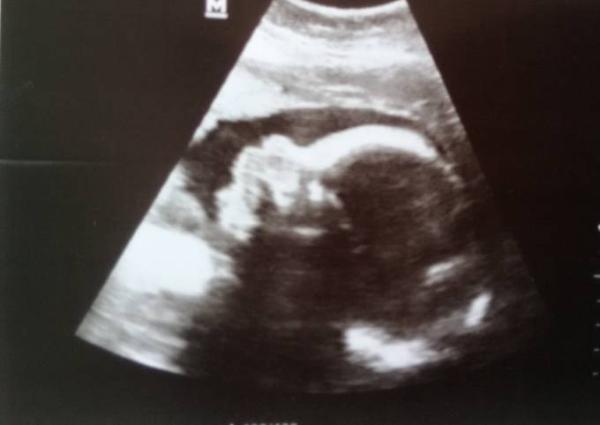

So, heute durfte ich auch endlich mal wieder nach dem Zwerg schauen. Er/Sie ist aber weiterhin schüchtern...na, dann halt nicht. Bei 31+1 ist es 1850g leicht und schon 42cm lang Keine Auffälligkeiten und wie ich schon vermutet hatte liegt der Kopf nun auch unten. Sehr zufrieden bin ich mit nur +2kg in den letzten 5 Wochen, damit bin ich jetzt insgesamt bei +12, damit kann ich leben. Ab jetzt geht es im Wechsel zur Hebamme und zum Arzt, bin sehr gespannt. Und weil der Tag noch nicht lang genug war, warte ich grad auf den Bus zum Vorbereitungskurs....bin ich froh, dass ich Mittwochs frei habe!